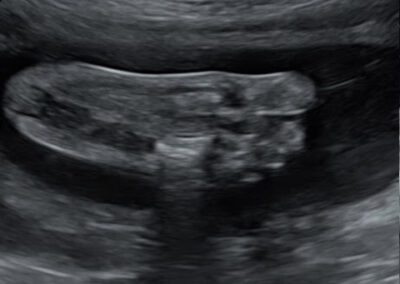

גלריה